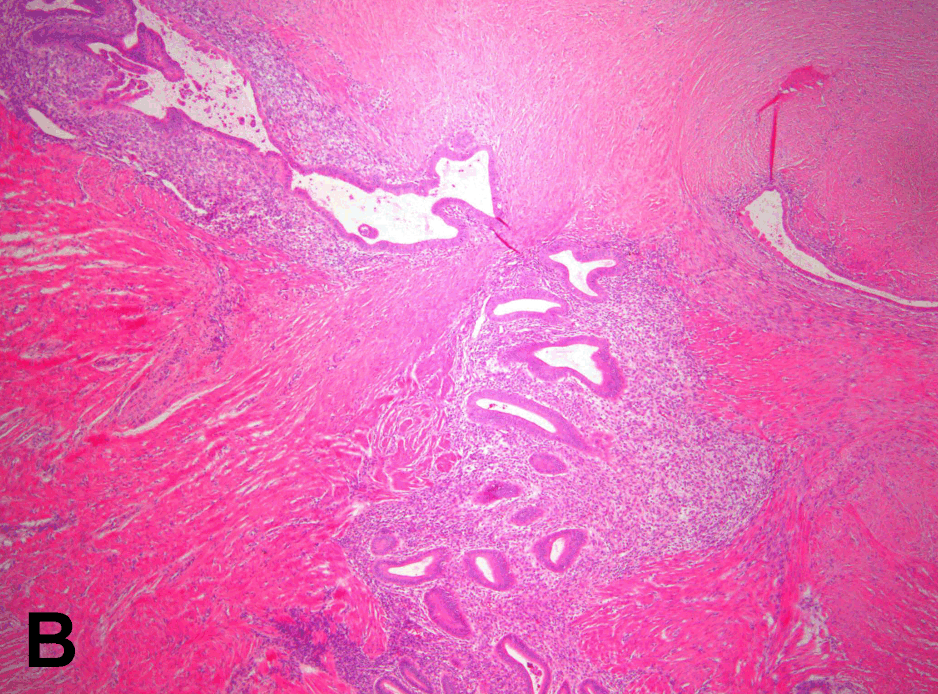

Histological examination of the resected ileum showed focal areas of superficial mucosal ulceration with destruction of glands and a neutrophilic infiltrate (Figure 3 A, B). Granulomas were not seen. Sections taken from the strictured ileum showed the presence of endometrial glands and stroma on the serosal surface of the bowel, extending into the outer half of the muscularis propria. There was associated fibrosis, scarring and distortion of the wall and the overlying mucosa. There was no evidence of dysplasia or malignancy. The area of polypoidal mucosa within the cecum appeared to be the mouth of the appendix which was also associated with endometriosis, fibrosis and scarring and had completely intussuscepted into the cecum. The diagnosis made was endometriosis with associated inflammation and stricture formation involving the distal ileum, appendix, cecum, ascending colon, omental fat and associated lymph nodes.

Figure 3: A, B) Histopathology of the small bowel showing an area affected by endometriosis.

A histological finding of note in our case is the finding of a polypoid mass that was actually an intussuscepted appendix in the cecum (Figure 3), which is a documented complication of endometriosis of the appendix. It is an extremely rare phenomenon [10] but worth noting as a differential diagnosis for a neoplasm since malignancy occurs in 0.7 to 1% cases of intestinal endometriosis. [11] Intussusception of the appendix is believed to occur as a result of endometrial tissue infiltrating the muscularis propria and leading to hypertrophy and hyperplasia. Strong peristaltic contractions due to the hypertrophic segment of the appendix can then force the appendix into the cecal lumen and cause intussusception of the appendix. [10] In our case the entire appendix had inverted into the cecum. An intussuscepted appendix may remain asymptomatic or can cause acute abdominal pain, a palpable mass in the lower abdomen or non-specific gastrointestinal symptoms like vomiting and diarrhea. [12] [13] In our case it was most likely an incidental finding.